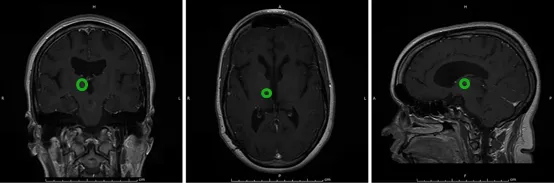

消融后9个月的磁共振成像MRI

消融后1年的磁共振成像MRI,几乎看不到肿瘤